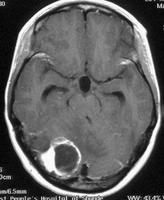

血管母細胞瘤可以用注射顯影劑的電腦斷層或是核磁共振掃描來加以診斷。在這些檢查中,注射顯影劑之後,血管母細胞瘤會在腦或是脊髓中顯現出亮白色的病灶。血管母細胞瘤往往會跟一些腫瘤很像,例如腦膜瘤、轉移性腦瘤或是一些血管病變,例如動靜脈畸形。

血管母細胞瘤會有兩種基本的形態,包括固體狀和囊泡狀的。固體狀腫瘤幾乎全部由細胞所組成,而囊泡狀腫瘤則是小部份的細胞伴隨著大部份的囊泡所組成的。